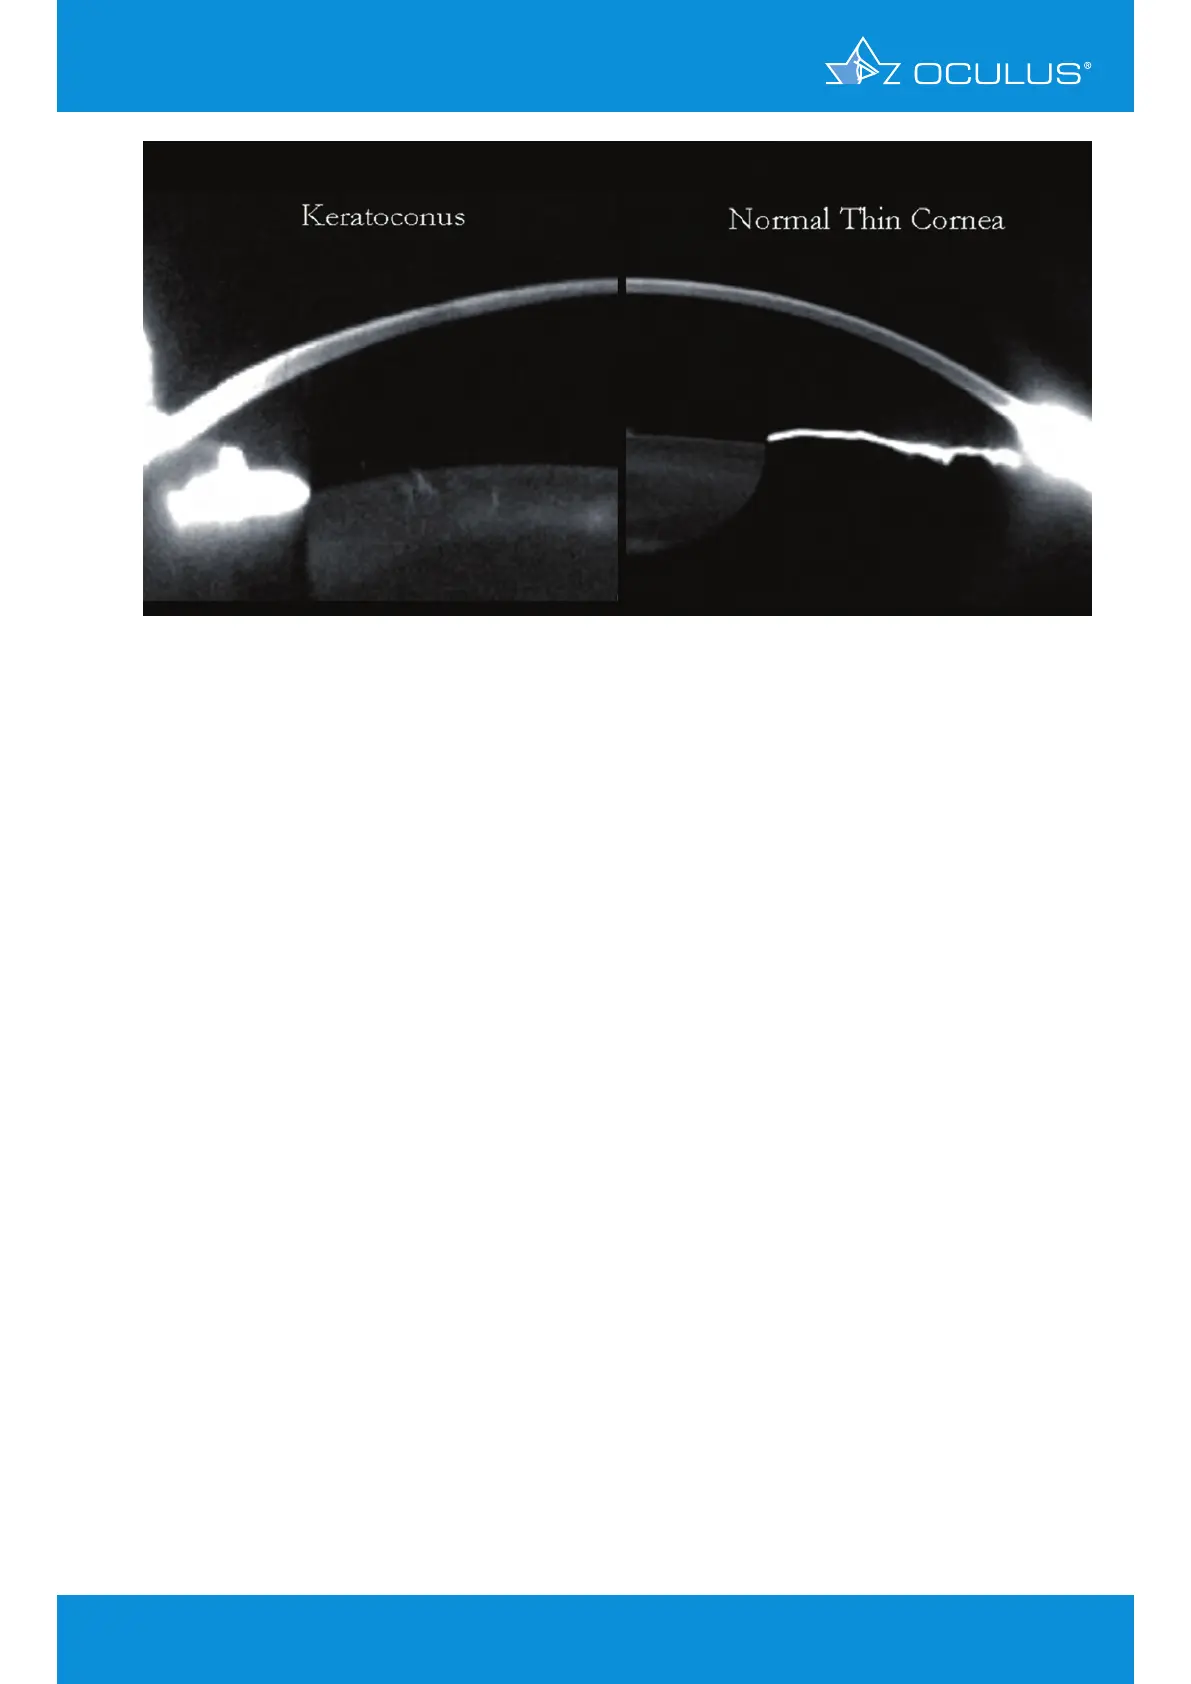

Figure 76: Thickness profile in an ectatic and a normal eye